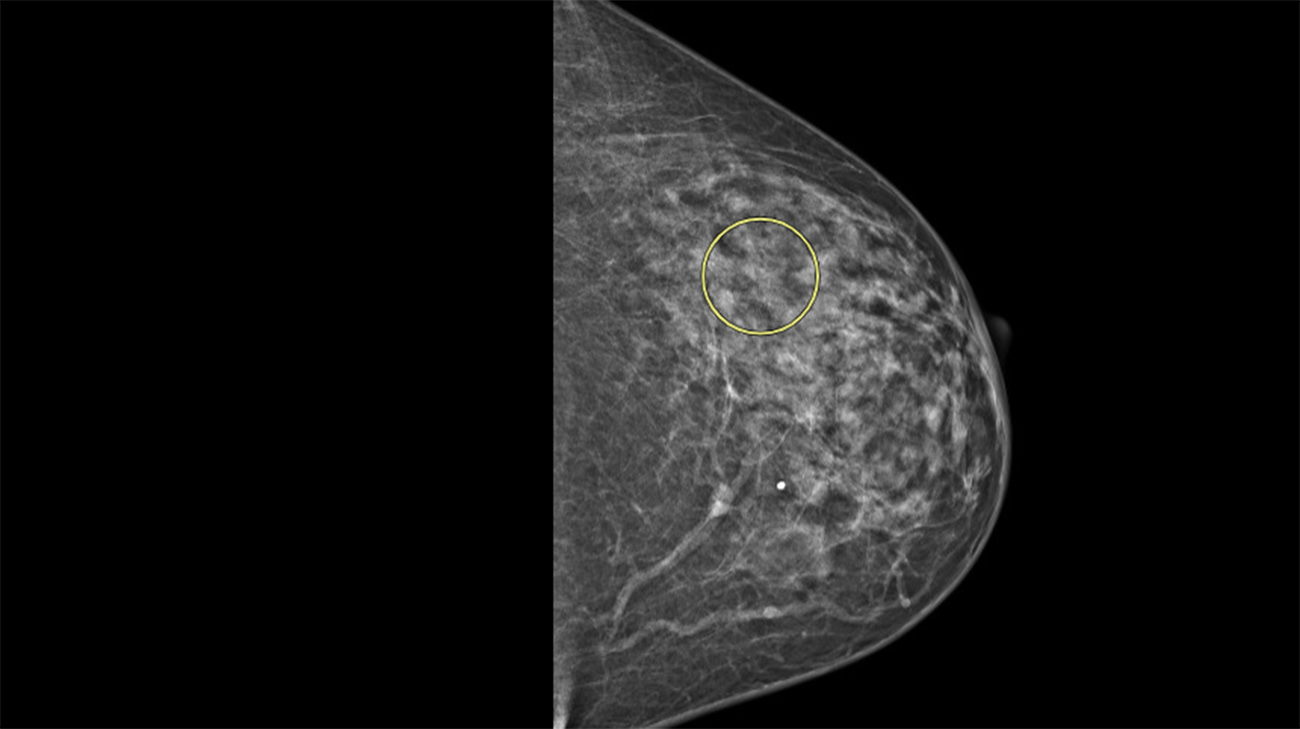

Those tests confirmed Tammy had invasive lobular breast cancer, a form of breast cancer that’s notoriously difficult to detect. Unlike ductal breast cancer, which typically forms noticeable lumps, lobular cancer grows in strands or webs of cells, often blending into surrounding tissue. Though it accounts for up to 15% of invasive breast cancers, it’s often referred to as “the sneaky breast cancer” because it can go unnoticed for longer periods.

A scan showing lobular breast cancer. (Courtesy: Cleveland Clinic)